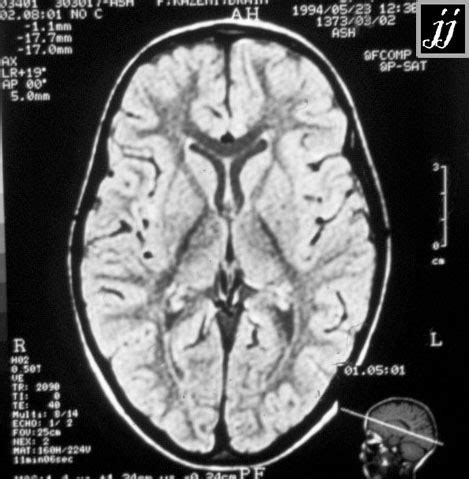

Alright guys, imagine you need to describe the location of something in your body. How do you do it precisely? That’s where anatomical planes and directional terms come in, and they are super important for understanding anatomy. Think of them as a universal language that scientists and doctors use. The first major plane is the sagittal plane . This plane divides the body vertically into right and left parts. If you draw a line straight down the middle of your nose and continue it down your body, that’s the median or midsagittal plane. Any plane parallel to this is a parasagittal plane. Then we have the frontal (or coronal) plane . This one divides the body vertically into anterior (front) and posterior (back) parts. Think of a crown worn on the forehead – that’s the coronal plane. Lastly, there’s the transverse (or horizontal) plane . This one divides the body horizontally into superior (upper) and inferior (lower) parts. This is like slicing a loaf of bread. Understanding these planes helps us visualize how structures are related to each other in three dimensions. Now, let’s talk directions. We use terms like anterior (front) and posterior (back) – basically front and back. Superior (towards the head) and inferior (towards the feet) refer to up and down. Medial means towards the midline of the body, while lateral means away from the midline. Think of your arms being lateral to your chest. Proximal and distal are used for limbs, with proximal meaning closer to the point of attachment or origin (like your shoulder is proximal to your elbow), and distal meaning further away (your fingers are distal to your wrist). We also have superficial (towards the surface) and deep (away from the surface). So, your skin is superficial to your muscles. Mastering these terms might seem a bit like learning a new language at first, but they are absolutely crucial for accurately describing and understanding anatomical locations and relationships. They remove ambiguity and ensure everyone is on the same page when discussing the human body. So, next time you hear about a structure being ‘anterior’ or ‘medial’, you’ll know exactly what that means!